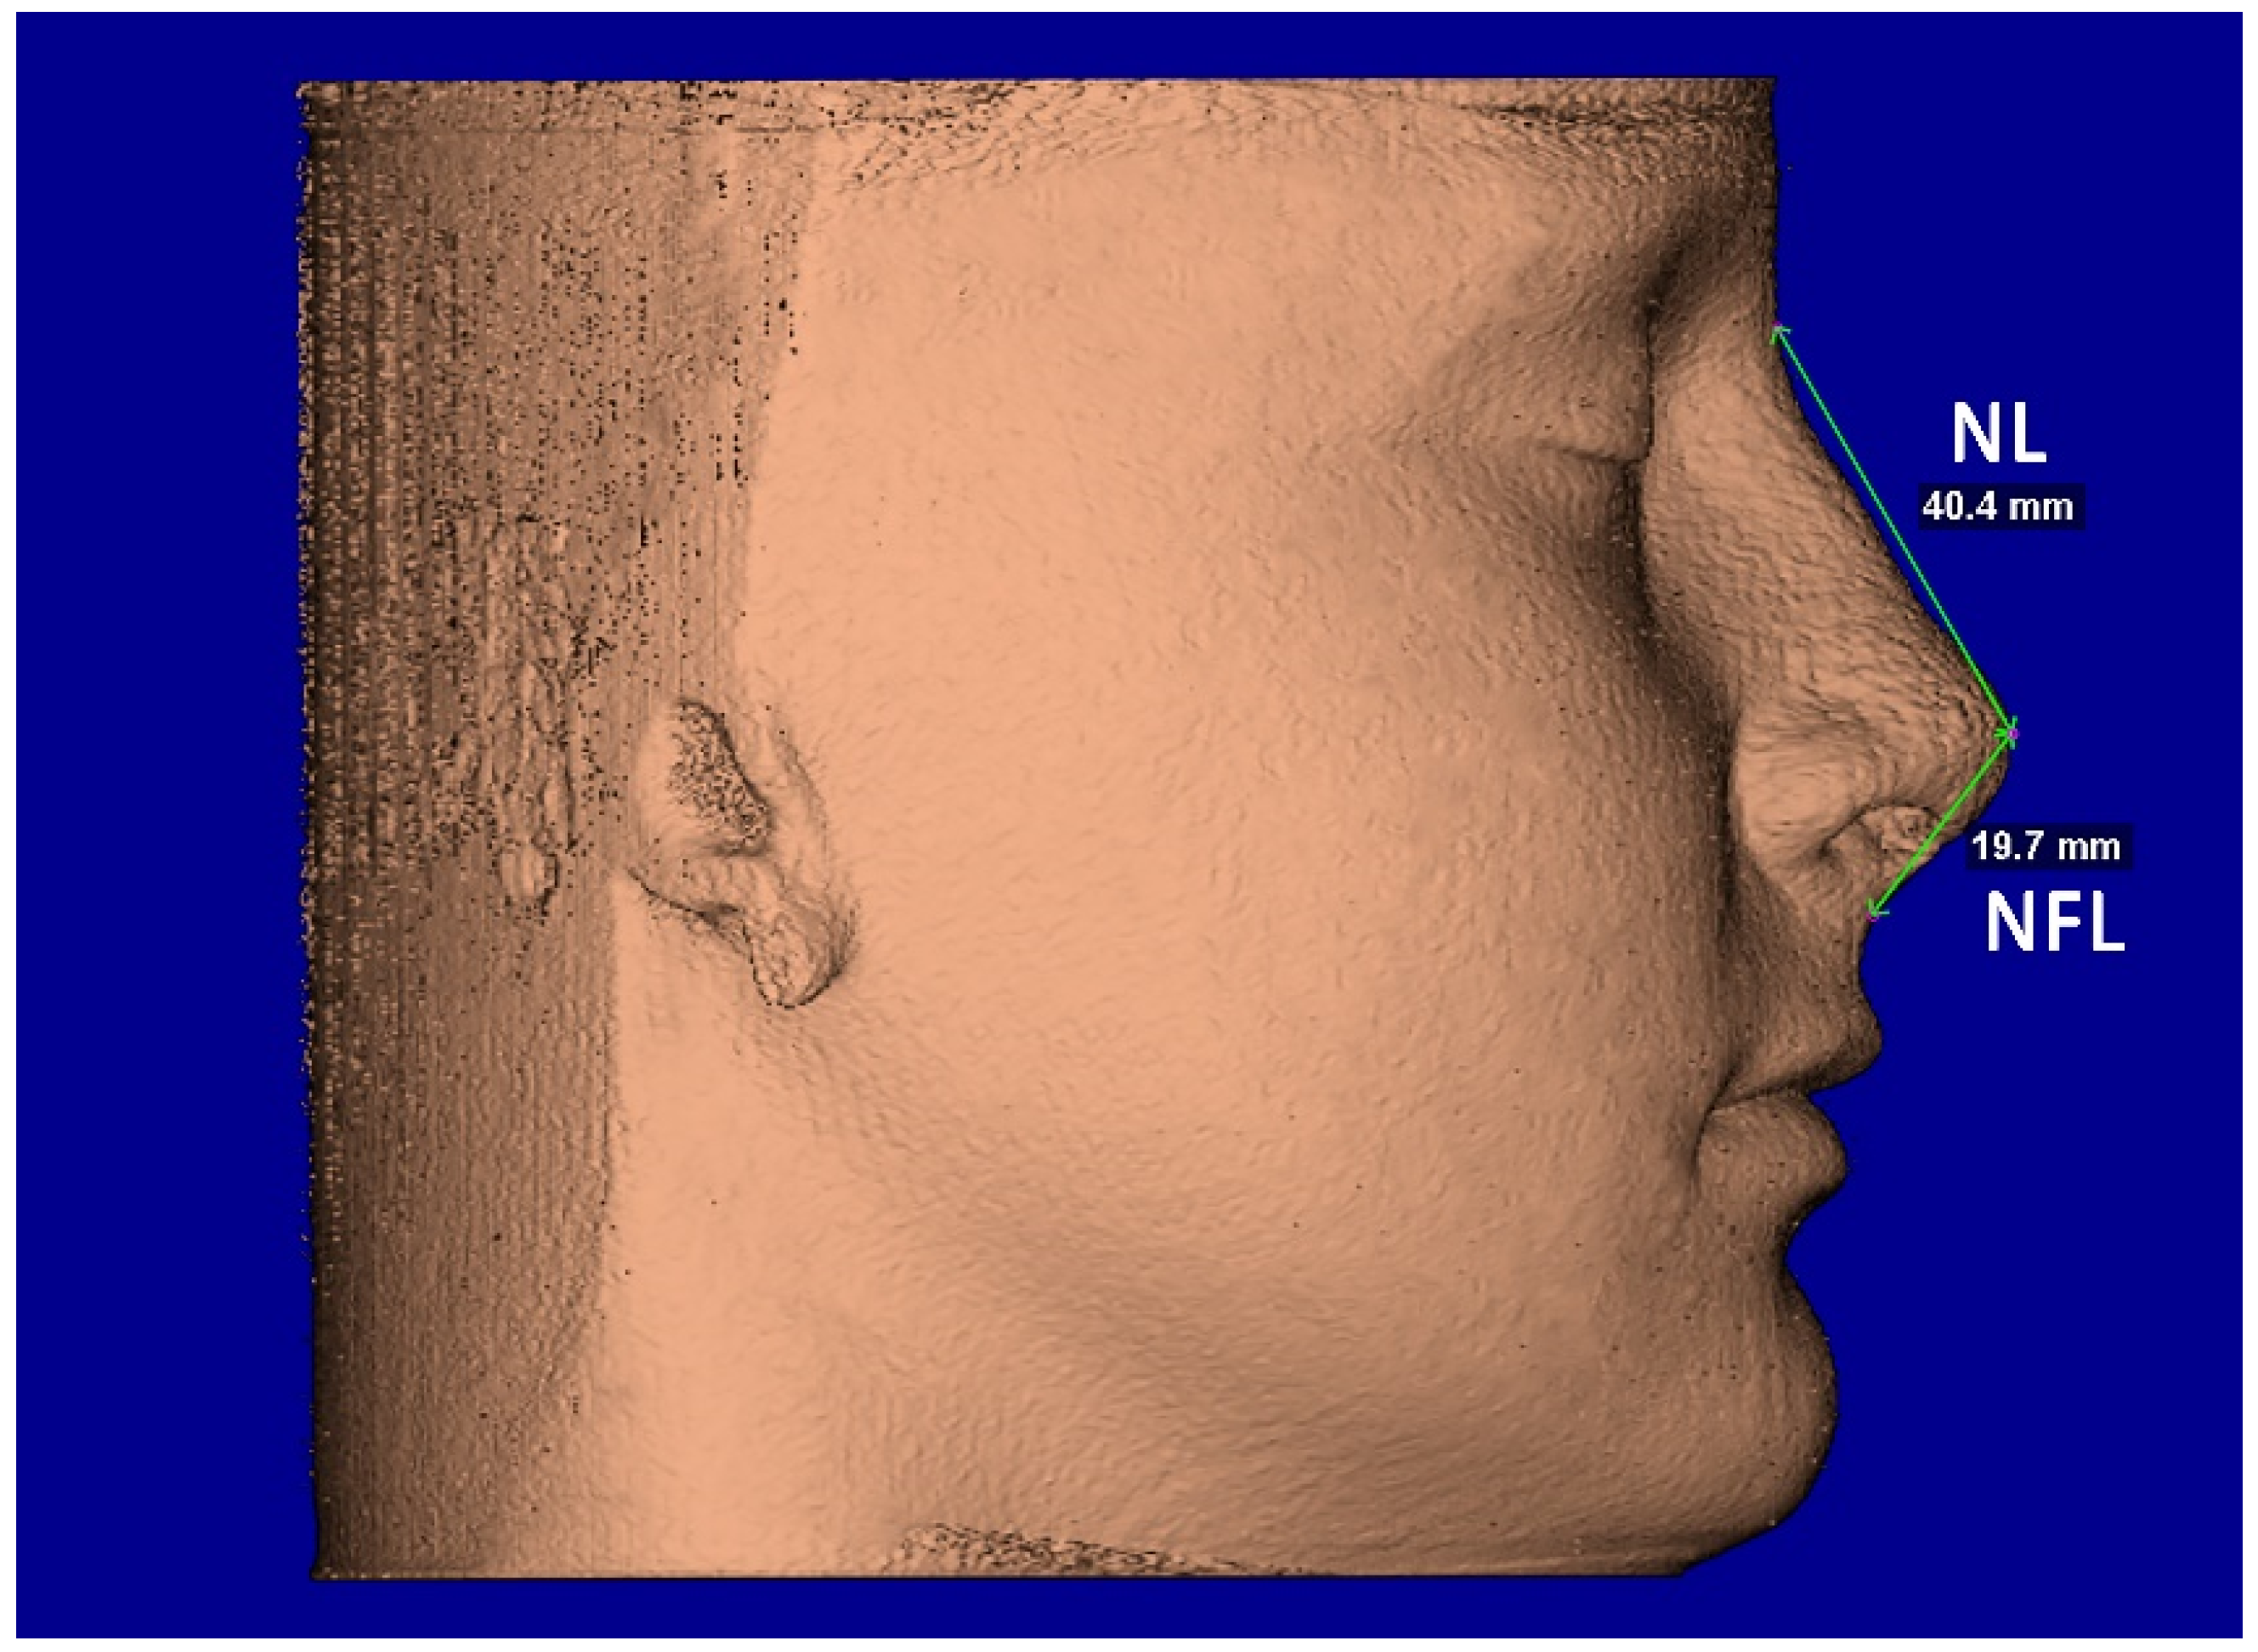

The segmentation mask of facial soft-tissue was created, setting the Hounsfield units threshold between −1024 and −200 and then converted into a 3D rendered model. The analysis of the nasal soft-tissue region was performed using the following measurements [17] (Table 1): Alar base width (ABW) (Figure 5), Alar width (AW) (Figure 5), Length of the nose (NL) (Figure 6), Length of the nasal filter (NFL) (Figure 6), Naso-labial angle (NLA) (Figure 7).

Figure 6.

Facial soft-tissue linear measurements of the length of the nose (NL) and length of the nasal filter (NFL).

A small increment of nasal length (NL), nasal filter length (NFL), and nasolabial angle (NLA) were found in both groups between T0 and T1; instead, a small reduction in the same measurements was recorded at T2. However, these changes were not statistically significant (p > 0.05) (Table 3). Finally, no differences were found between the TB and BB groups in the changes of NL, NFL, and NLA recorded at 6 months (T0–T1) and 1 year (T0–T2) after maxillary expansion (p > 0.05) (Table 4).

4.2. Post-Retention Sagittal Changes

Another assumption of this study is the possibility that RME, in the form of TB and/or BB anchorage, can change the sagittal projection of the soft tissue in the nasal region. A small increment of nasio-labial angle, nasal filter, and nasal length was found in both TB and BB groups; however, these findings were not statistically significant as well as they did not differ between the two groups. As far as we know, the only study that looked at the height of soft tissue in the nose was that of Magnonson et al. [18]. In that study, the authors found an insignificant increase (p > 0.05) of 0.18 mm, but in contrast to our study that observed changes after RME, they were observing changes following surgical disjunction. Nevertheless, despite being not statistically significant, the increment of nasio-labial angle, nasal filter, and nasal length data were consistent and could be attributed to adaptive postural changes to accommodate the width and thickness of the expander appliance [24].